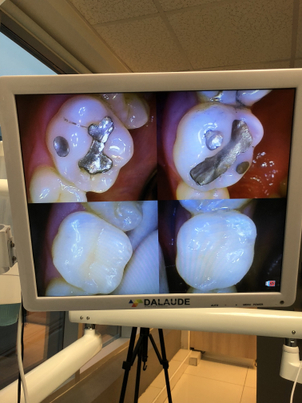

Paciente tratada por la Dra. Katherine Ruiz

La endodoncia es un tratamiento que requiere de máximo profesionalismo, pues un procedimiento mal hecho puedo tener consecuencias importantes para la salud del paciente. Por otro lado, la experiencia, habilidad y capacidad del endodoncista o del dentista es fundamental y determinante para conseguir un buen resultado que además sea duradero.

Al tratarse de un procedimiento un tanto complejo, es vital que el paciente acuda a un profesional capacitado para llevar a cabo este tipo de intervenciones con el máximo cuidado y equipos y materiales de buena calidad. Al momento de elegir al endodoncista o dentista que llevará tu caso, es importante que te asegures de: